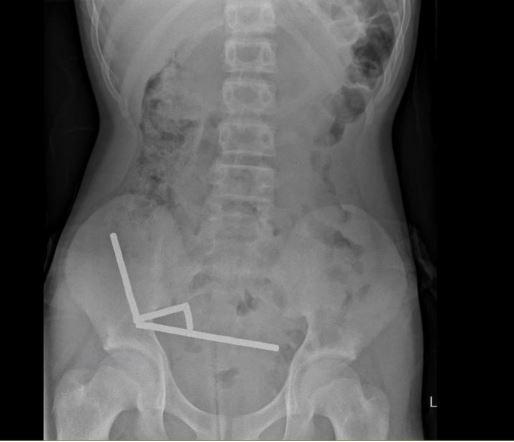

En el análisis físico, presentaba alta sensibilidad en el cuadrante inferior derecho de su abdomen, lo que fue confirmado por la radiografía abdominal, que reveló “cuatro cadenas lineales de imanes localizadas en el cuadrante inferior derecho del abdomen. Estas parecían ser partes separadas del intestino adheridas entre sí debido a las fuerzas magnéticas”.

En esta línea, en la publicación se detalla que los imanes estaban causando necrosis por presión en el ciego (la primera porción del intestino grueso) y dos áreas del intestino delgado. Por lo anterior, “se realizó una resección ileocólica y dos resecciones en cuña del intestino delgado para recuperar los imanes”.